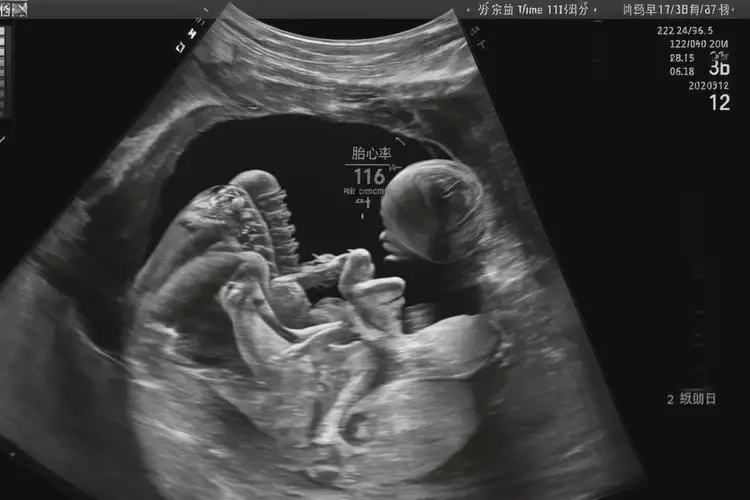

孕33周6天胎心116正常嗎

胎心116次/分鐘在孕33周6天屬于偏低范圍。

胎心率是指胎兒心臟每分鐘跳動的次數(shù),正常情況下,胎心率在孕期會有一定的波動范圍。在孕33周6天時,正常的胎心率范圍通常在120-160次/分鐘之間。胎心116次/分鐘低于正常范圍,可能需要引起關(guān)注。

孕33周6天胎心116正常嗎(圖1)